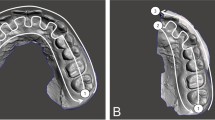

Orthodontic diagnostic setups were constructed according to their respective treatment plan, outlining anchorage requirements and incisors’ end-of-treatment goal positions. Interproximal reduction necessary to achieve the treatment plan was performed considering Bolton discrepancy and arch size discrepancy to achieve ideal positions of teeth and normal intra- and intermaxillary relations according to Andrews’ six keys of normal occlusion [22] (Fig. 1). All setups were performed by one investigator, who had proper training in both methods to ensure standardization.

Digital diagnostic setups were constructed using the OrthoAnalyzer program (3Shape, Copenhagen, Denmark), following the protocol demonstrated by Sung et al. [8]. The digital setup was subsequently exported and saved as STL files for later review and 3D printing.

Digital setup STL files were imported into the Appliance Designer Program (3Shape, Copenhagen, Denmark) for trimming and the addition of ID tags to the models. The Vlare slicer program (Vlare Technology Co., Shenzhen, China) was utilized to prepare virtual diagnostic setup files for 3D printing. The STL files of the digital setups were exported to an M10-8 K LCD 3D printer (IN3D.Co, Egypt). Proshape 405 nm UV resin (Proshape Digital Solutions, Turkey), a ceramic-based water-washable LCD printer resin, was used for printing the models. The 3D models were hollowed with a 2 mm wall thickness.